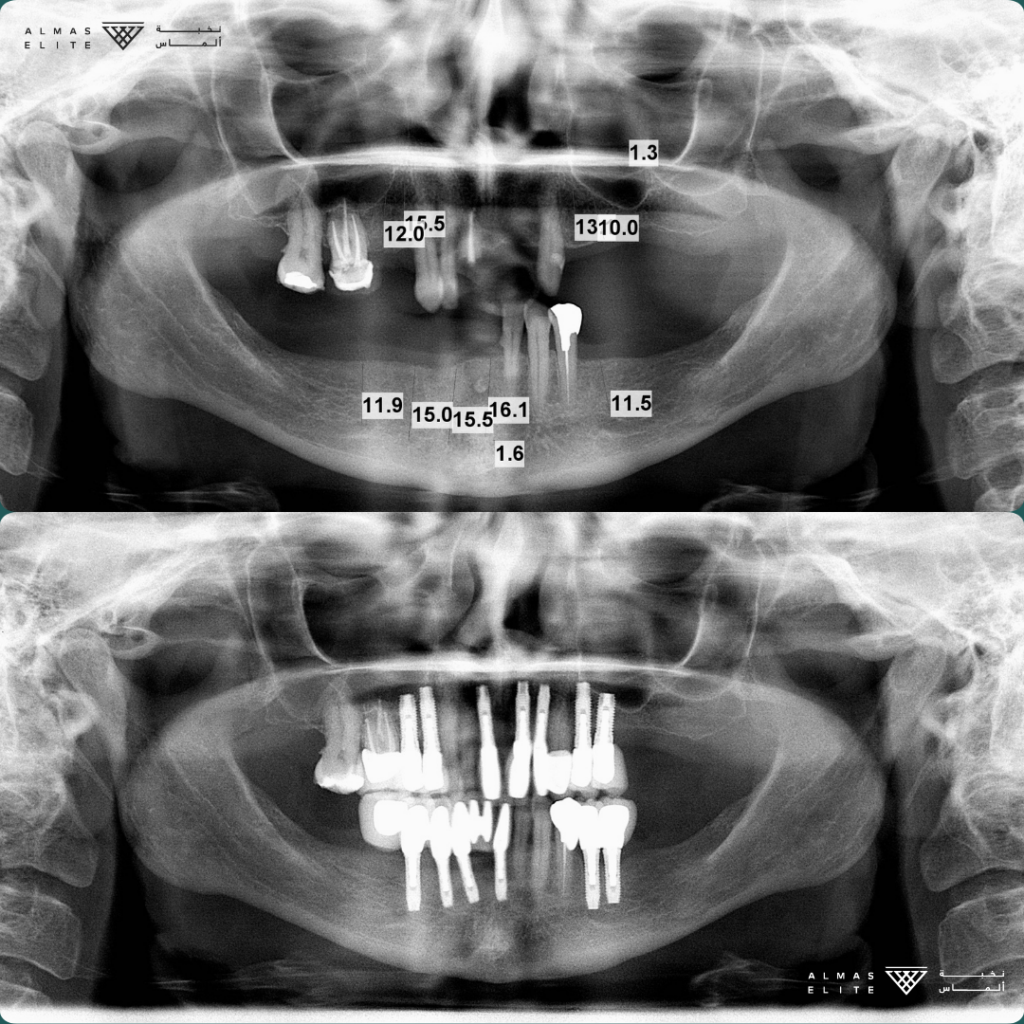

القرار النهائي لملاءمة الزراعة يتم بعد استشارة الطبيب، والفحص السريري، والتصوير الإشعاعي (مثل الأشعة ثلاثية الأبعاد) حسب الحاجة.

• الفحص الكامل: يشمل الأشعة ثلاثية الأبعاد وتحليل جودة وكثافة العظم.